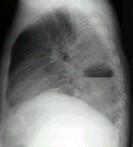

问题 男,36岁,胸痛半月伴发高热,胸片发现占位性病变,CT检查如图,最可能的诊断为 ( )

选项 A.左下肺肺脓肿 B.左下肺癌并空洞形成 C.左侧胸腔积脓 D.左下肺囊肿 E.左下肺肺炎

答案 A